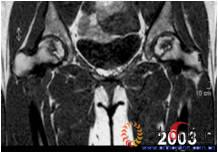

2.2 影像学结果 影像学结果与临床结果基本同步。临床结果优的36髋,34髋维持圆形且修复较完全(图1)。1例双髋Ⅲa激素性(SARS患者)ONFH,术后随访7年8月,X线片显示股骨头虽不圆,但临床HHS评分90分为优(图2)。功能为良的12髋,7髋股骨头不圆,但股骨头与髋臼匹配好,其余5髋股骨头维持圆形。临床评定为差的17髋,股骨头均有超过4mm塌陷,股骨头与髋臼匹配不好,股骨头内无折断,MRI未显示骨髓水肿,关节间隙呈不对称改变,CT扫描示软骨下骨折,MRI显示骨髓水肿。

图1 女,22岁,(1)双侧股骨头坏死右侧B型,左侧C1型;(2)打压植骨术(加入BMP2)后5年,CT显示植骨生长良好,关节功能正常(Harris评分96分);(3)术后7年关节功能维持正常,股骨头维持正常外形